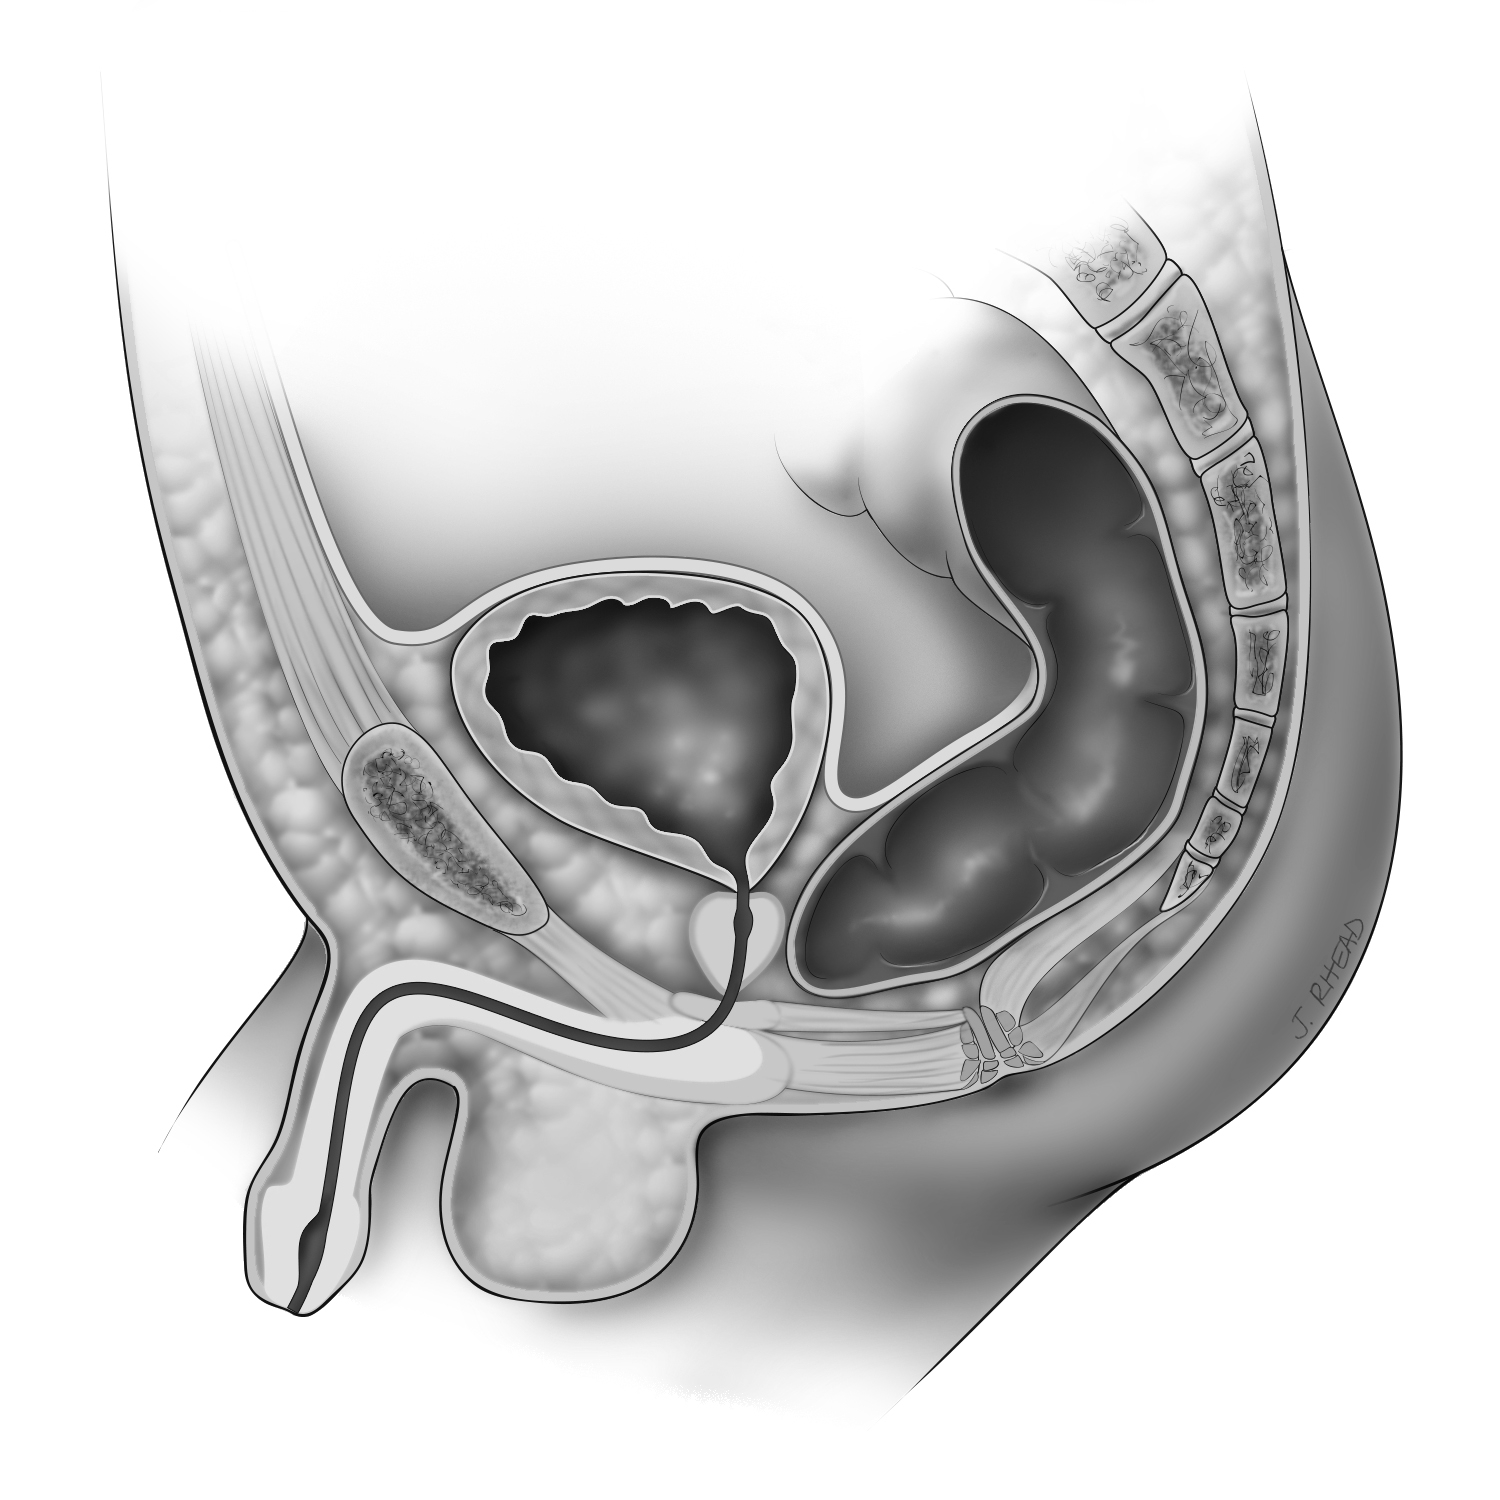

Rectobulbar Fistula

The rectum connects to the urethra in a male; there is no opening on the bottom